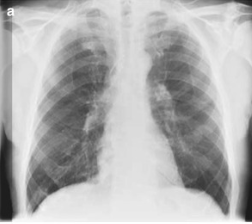

Important

Among febrile neutropenic patients with a “normal” chest X-ray, up to 60% may have findings of pneumonia on CT scanning.

Figure 18: Normal chest X-ray in a neutropenic patient with occult pneumonia

Figure 19: CT scan revealing pulmonary infiltrates not visible on chest X-ray